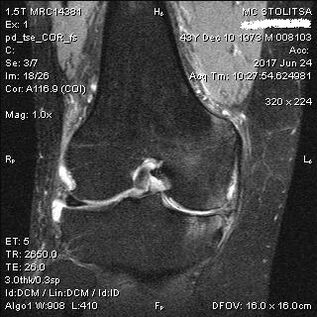

Diagnosis of arthrosis of the knee joint takes place in the office of a rheumatologist or orthopedist.The doctor examines the affected joint, palpates it, listens to complaints and asks additional questions.Performs several tests - for example, asking the patient to bend his leg or walk a few steps.Then, if it is necessary to clarify the stage of the disease or the nature of pathological changes, he will refer you for additional studies.For example, for computed tomography or radiography.